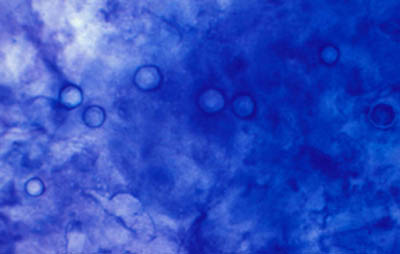

A - CW B - Giemsa C - PAS D - Gram

Tinción CW

Blanco de Calcofluor + Azul de Evans

Magnificación 160x